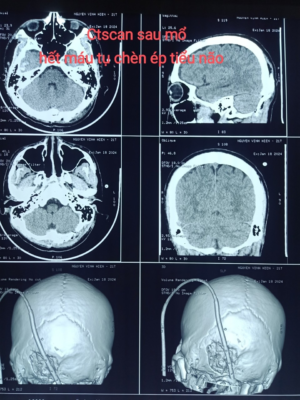

Ca mổ diễn ra thuận lợi, lấy khối máu tụ, giải phóng chèn ép tiểu não. Kết quả Ctsccan sau mổ sạch máu tụ.

Hình 3. Máu tụ được lấy bỏ Hình 4. CT scan sau mổ

Hết chèn ép tiểu não

Ngay sau mổ tỉnh táo hoàn toàn, vận động bình thường, không có các rối loạn hay khiếm khuyết thần kinh.